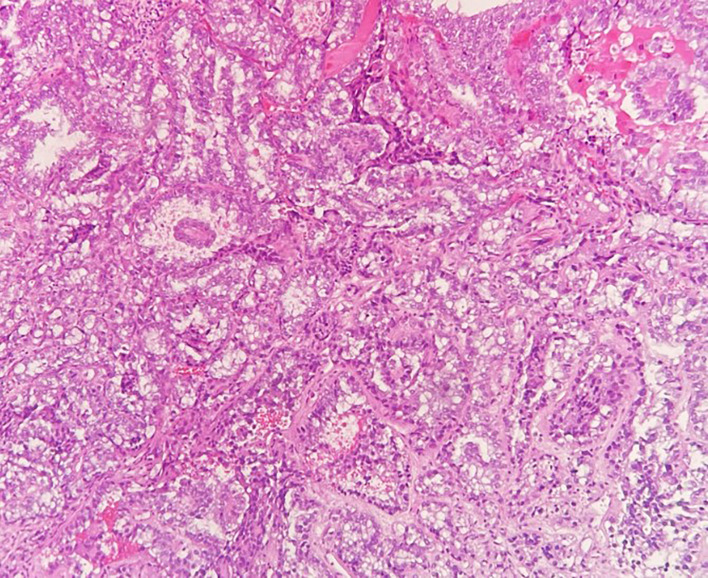

一名49岁患者被诊断出患有4cm的阴道透明细胞腺癌(VAC),肿瘤浸润骨盆侧壁(图1、2)。初步诊断时,在计算机断层扫描(CT)中检测到多发性肺转移瘤,大小可达5 mm。由于转移灶体积小,CT引导下穿刺肺转移灶似乎不可行。原发肿瘤的免疫组化显示激素受体阴性,p16表达阴性,Ki-67高达70%。由于局部晚期、无法手术的VAC伴右腿转移性疼痛,使用卡铂AUC5/紫杉醇80 mg/m²和贝伐单抗15 mg/kg q3w进行全身治疗。临床和图像形态学肿瘤消退。在完成六个周期的化疗后,继续贝伐单抗15mg/kg维持治疗。临床检查和影像学检查显示,单用贝伐单抗15 mg/kg四个周期后,局部和肺部疾病进展。重复肿瘤活检免疫组织化学显示所有错配修复蛋白稳定,PD-L1联合阳性评分(CPS)为2,ERBB2表达。

图2. 苏木精和伊红染色的透明细胞腺癌活检